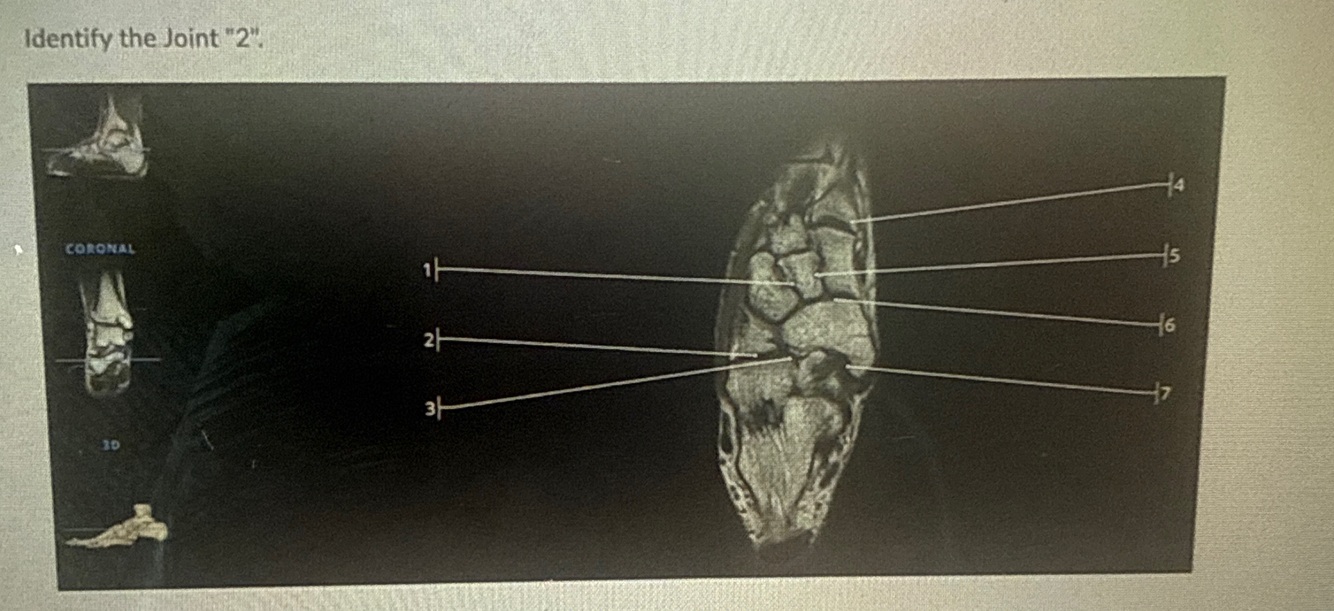

3

Q

Arrow points to

A

Deltoid ligment